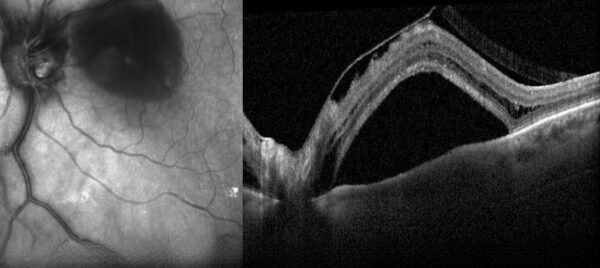

Figure 1: SD-OCT (Heidelberg Engineering®) of the left eye showing the presence of vitreoretinal traction with subretinal and intraretinal fluid.

Spectral domain optical coherence tomography (SD-OCT) revealed the presence of vitreoretinal traction with subretinal and intraretinal fluid in the LE (Figure 1).